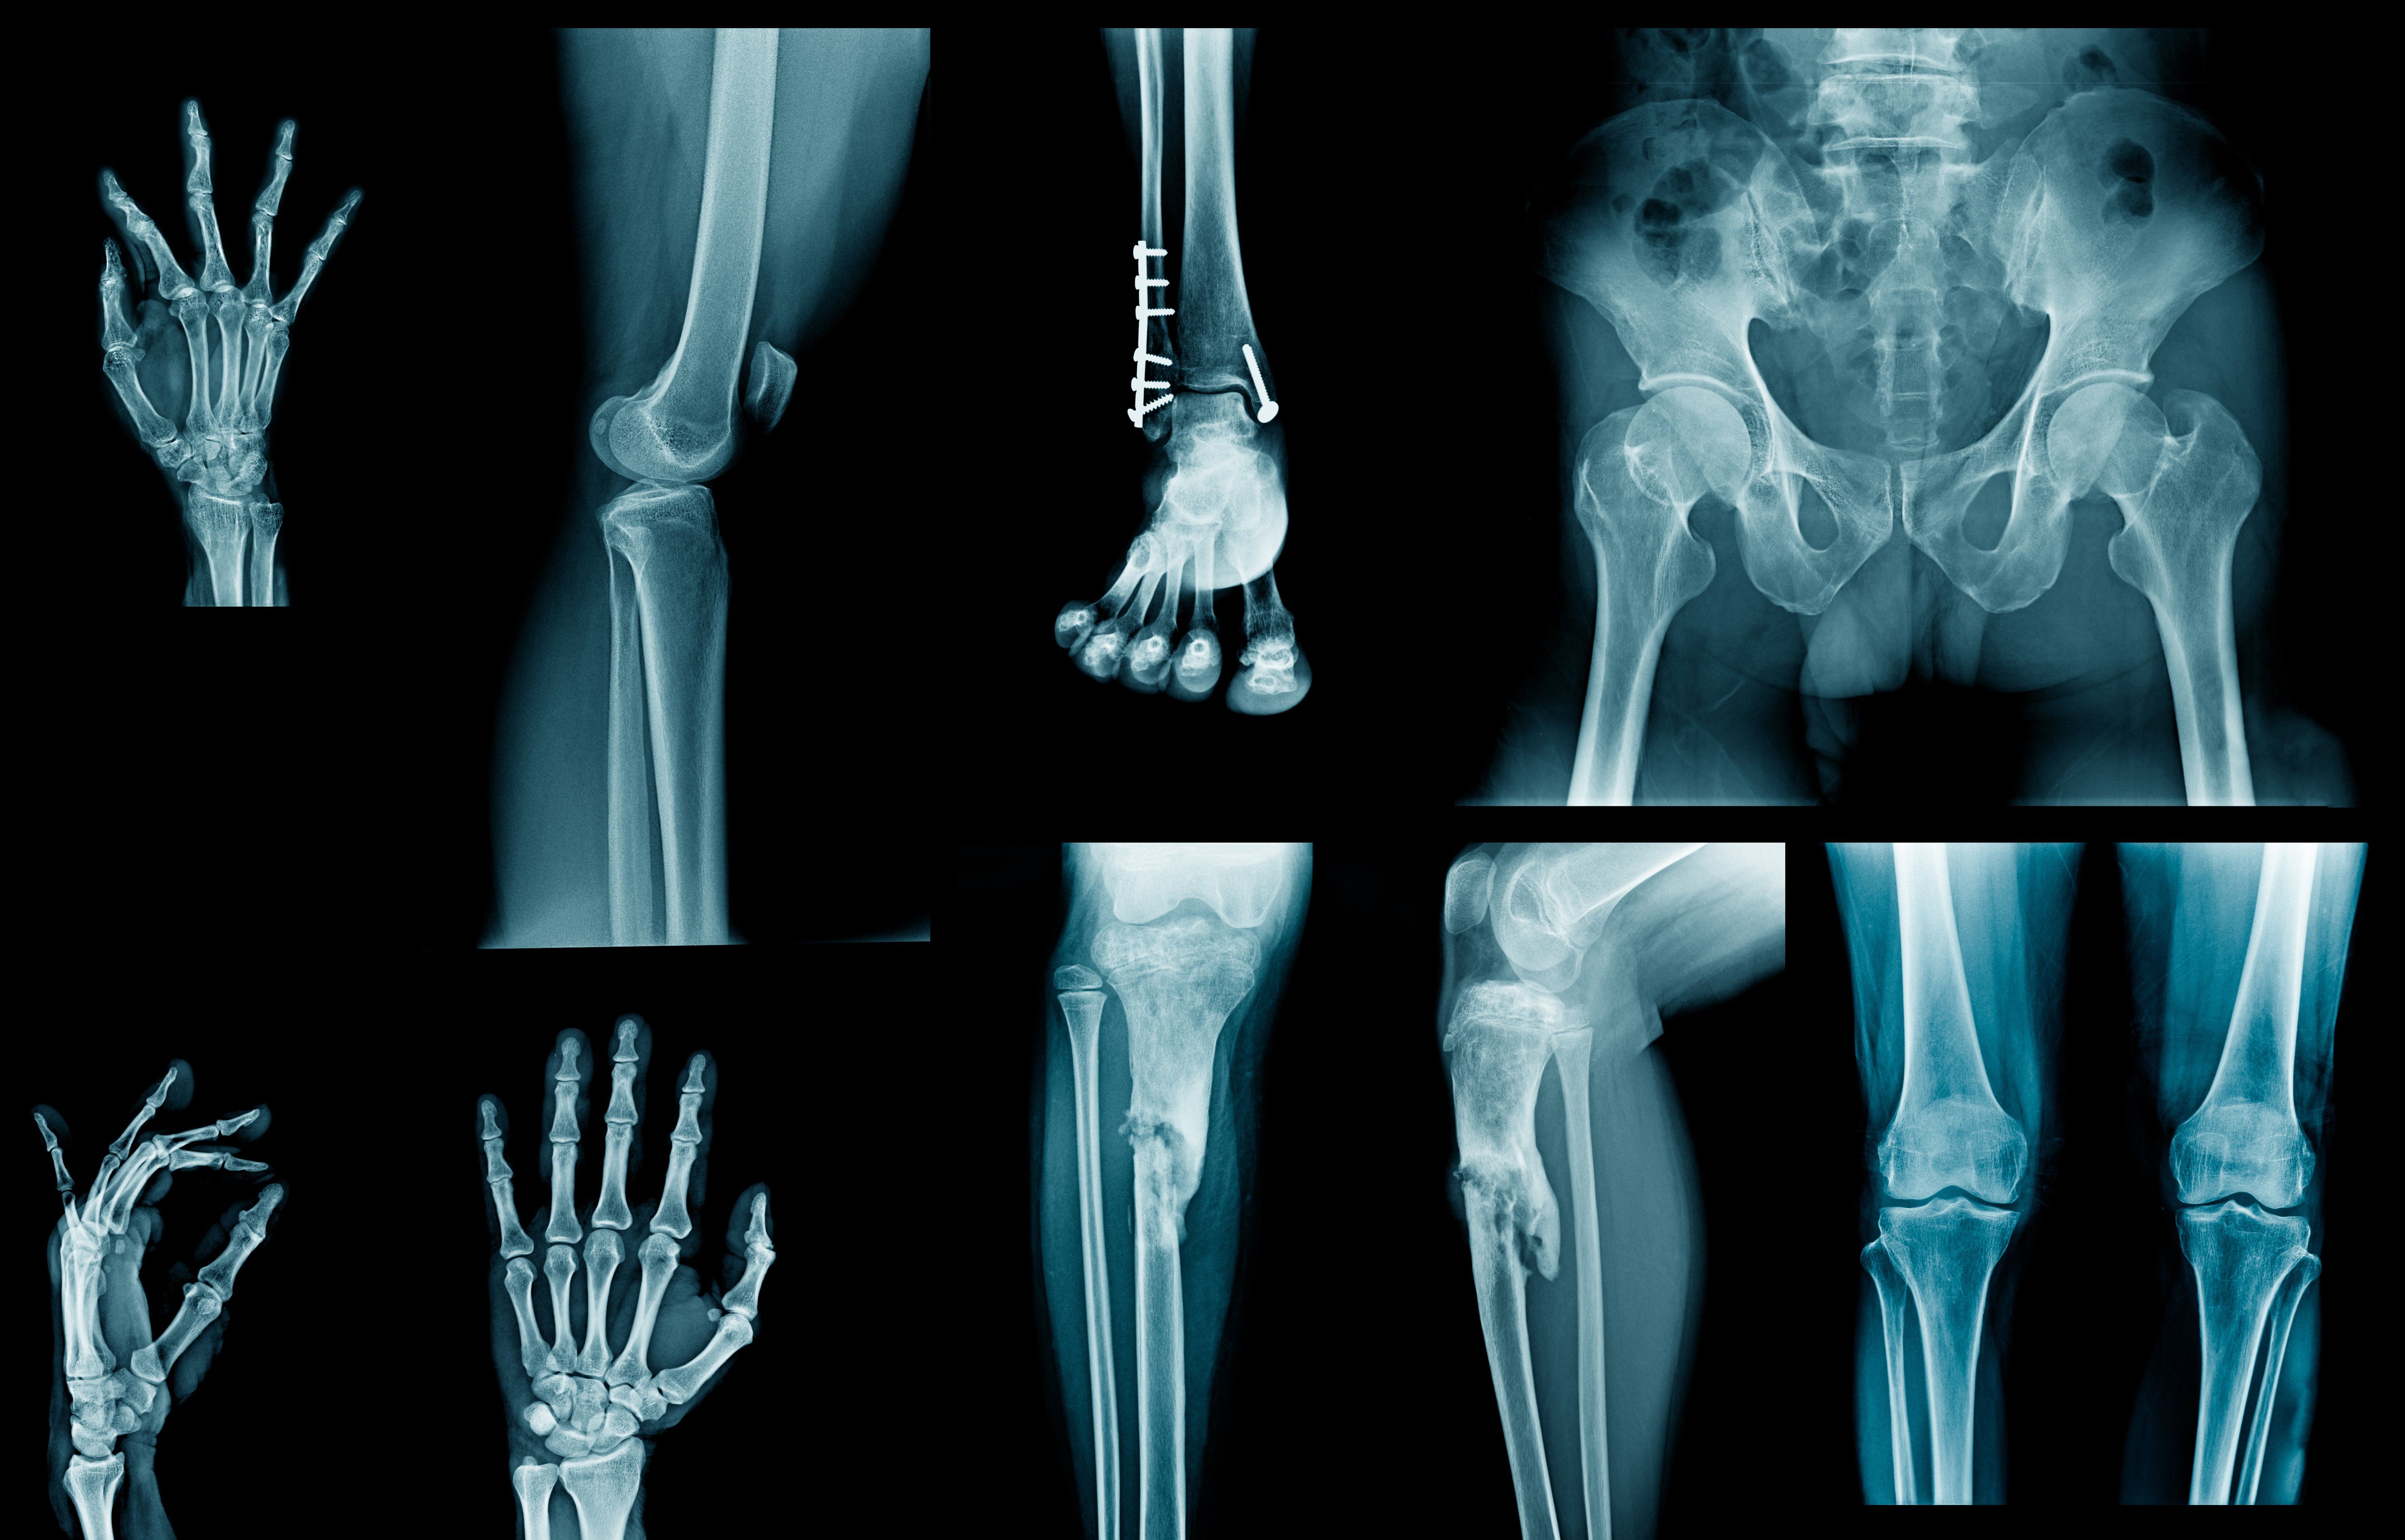

- Case Studies X Ray Imagecare - 3 Bone Tumours Vertebrae Flat Bones Long Bones Osteoid Osteoma Metastasis Epiphysis:

X Ray Examination Of The Long Bones Of The Case Described Download Scientific Diagram. Special cases of ankle fractures. It requires an injection of a small amount of radioactive fluid all films are returned to the radiology department at the nuffield orthopaedic centre for reporting. Please allow two weeks for the results to be sent to. Sometimes a fourth (delayed/delayed) phase is performed. From a study of the age prevalence of 4,000 malignant bone tumors, he gives the following table keep in mind that the classic descriptions of bone tumors that you spend so much time studying are for untreated lesions. Adjacent dentigerous cysts with the ectopic displacement of a third mandibular molar and supernumerary (forth) molar: Beek, radiologist, radiology department of the wilhelmina. Mri examination of the ankle. Case library case library by month. Study flashcards on radiology assistant: Learn what you might experience, how to prepare for the exam, benefits, risks and skeletal scintigraphy helps to diagnose and evaluate a variety of bone diseases and conditions using small amounts of radioactive materials called. Radiology department of the university medical centre of utrecht and the interactive digital education (part i), f.j.a. Current and accurate information for patients about bone scans. Erik beek and robin smithuis. What kind of lesions do radiologists spend most of their time looking at?